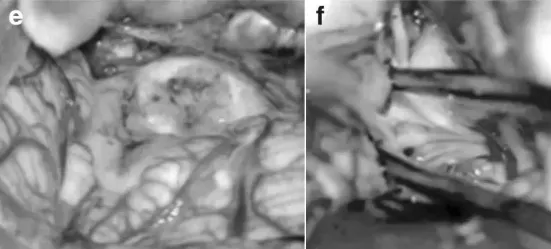

小A随后被推进手术室,主刀医生正是他们前期了解的巴特朗菲教授。在术中磁共振系统辅助下,巴教授采用俯卧位为小A实施手术。通过后正中位和左侧枕下颅骨切开术暴露肿瘤,使用CUSA刀切除病灶。在左侧外侧隐窝区域,肿瘤基底与颅神经根部粘连,术中将肿瘤与颅神经成功分离。巴教授特别谨慎处理后组颅神经,重点保护吞咽功能。最终,颅神经获得完好保留,尤其是第九、十、十一对颅神经保护良好。